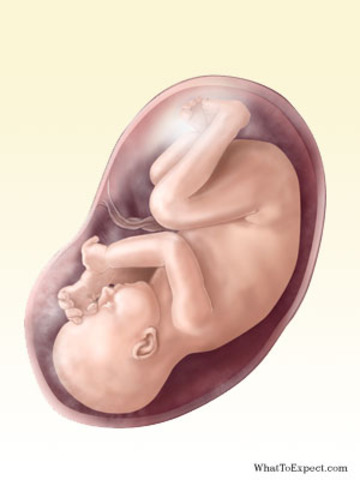

• Week 36

Week 36

Your baby, who is now about six pounds and 20 inches long, with soft bones and cartilage to allow a safer journey through the exit door. Most of her systems are ready for prime time, though her digestion system — which has done only practice runs so far — will kick into gear as she takes her first suckle at the breast or bottle.